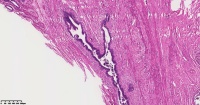

炎性息肉?潴留囊肿?腺体是否有问题?

性别

女

年龄

51岁

临床诊断

一般病史

宫颈赘生物

标本名称

大体所见

息肉。

稳妥起见最好做一做免疫组化。